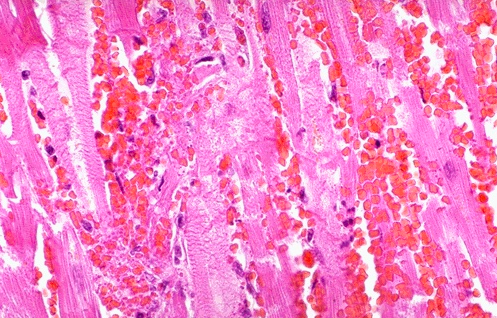

- In this microscopic view of a recent myocardial infarction, there is extensive hemorrhage along with myocardial fiber necrosis with contraction bands and loss of nuclei